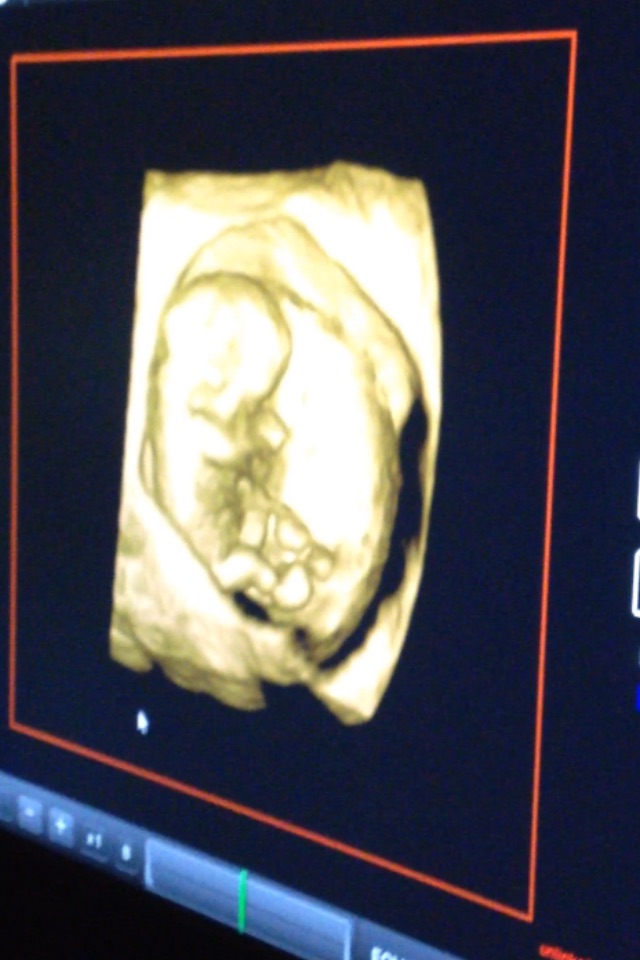

• We hit 11 weeks tomorrow and had our latest US appointment yesterday. We REALLY lucked out because our doctor got a new 3D ultrasound machine and tried it out on us. It was so awesome!!!!!